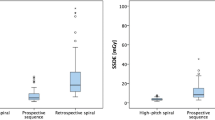

Overall mean IQ per segment rating was 1.45 ± 0.36, IQ rating of the large epicardial segments reached a mean of 1.33 ± 0.35, and both showed no significant differences between the study groups. Analysis of the small segments delivered an overall mean per segment score of 1.62 ± 0.43. Post hoc tests of the small segments resulted in a significant difference between the rECG and the pECGsys group (1.50 ± 0.40 vs. 1.70 ± 0.43, p = 0.02). Mean per segment score of the pECG group was 1.65 ± 0.48, with no statistical significance compared to the other groups (Fig. 1; Table 3).

Radiation dose

Group comparison of the radiation dose values showed significant differences between pECG vs. pECGsys (p < 0.001) and rECG vs. pECGsys (p < 0.001) (Fig. 2; Table 4). In pECGsys, one patient was examined at 80 kV, 22 patients were examined at 100 kV, 25 patients were examined at 120 kV and one patient was examined at 140 kV.